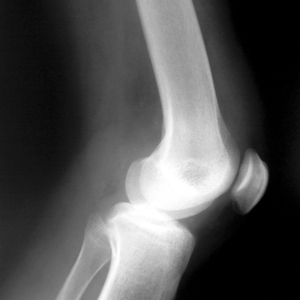

Proč vlastně křupe a lupe v kloubech?